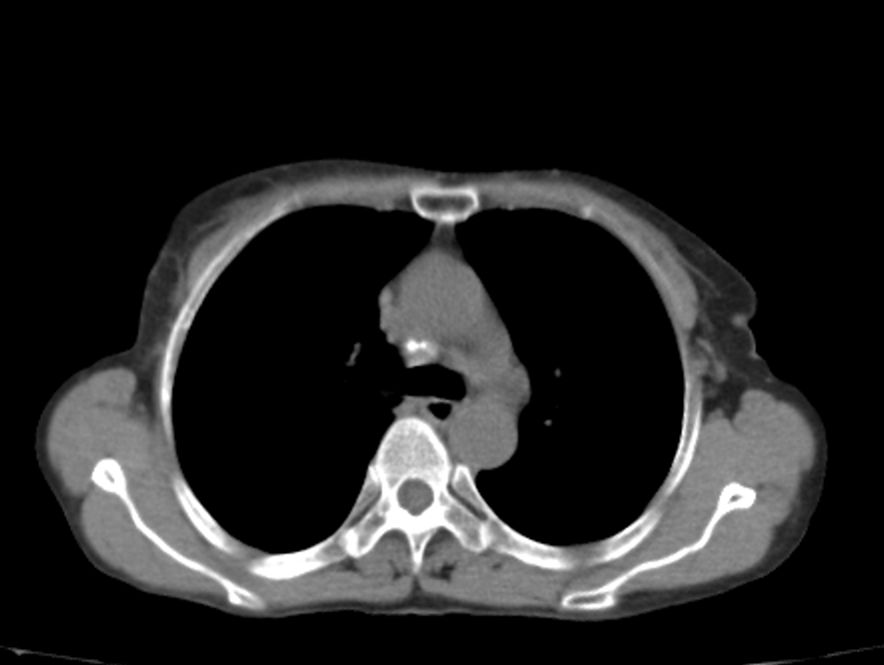

标题: CT21609:右乳包块1年,请各位讨论分析一下,乳腺CA, [打印本页]

标题: CT21609:右乳包块1年,请各位讨论分析一下,乳腺CA,

考虑---右乳癌并胸壁、肋骨、双肺转移。

考虑乳腺癌侵犯肋骨、胸壁及两肺转移可能性大。

右乳癌并胸壁、肋骨、双肺转移。

考虑右侧乳腺癌侵犯肋骨、胸壁及两肺转移。

支持考虑---右乳癌并胸壁、肋骨、双肺转移。

考虑右侧乳腺癌侵犯肋骨、胸壁及两肺转移可能。

考虑右侧乳癌并胸壁、肋骨及双肺多发性转移。